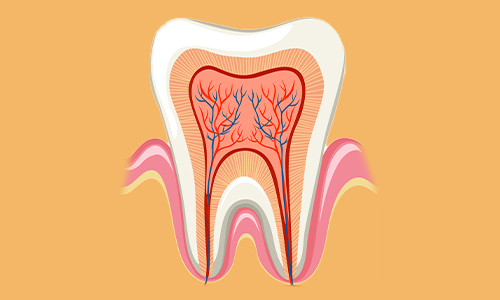

RCT - Root Canal Treatment